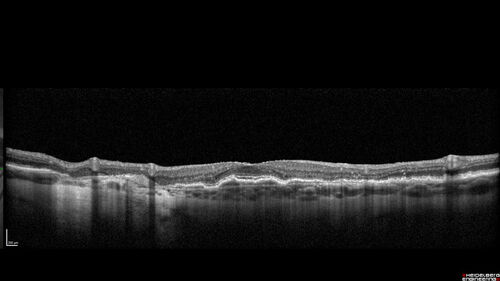

Fresh BRAO in patient with wet AMD

91 year old female She noticed last night a shadow over the left eye. When she closes her right eye she cannot see the bottom of the vision in the left eye. This is new.

VA OD: sc20/32-1

VA OS: sc20/32-2

BRAO in patient under treatment for wet AMD